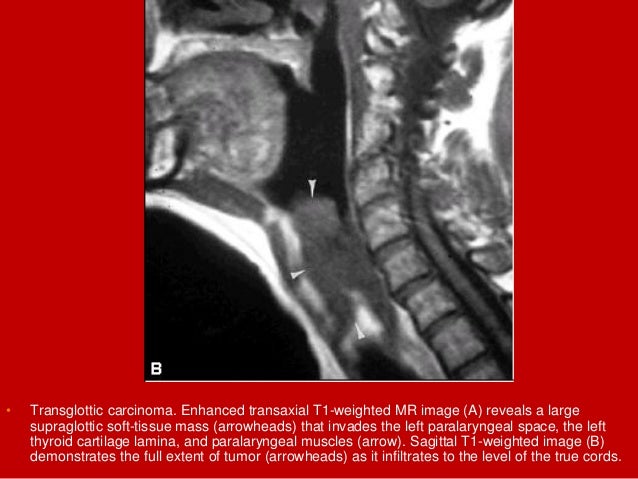

41. 41. • Transglottic carcinoma. Enhanced transaxial T1-weighted MR image (A) reveals a large supraglottic soft- tissue mass (arrowheads) that invades the left paralaryngeal space, the left thyroid cartilage lamina, and paralaryngeal muscles (arrow). Sagittal T1-weighted image (B) demonstrates the full extent of tumor (arrowheads) as it infiltrates to the level of the true cords.

42. 42. • Transglottic carcinoma. Enhanced transaxial T1-weighted MR image (A) reveals a large supraglottic soft-tissue mass (arrowheads) that invades the left paralaryngeal space, the left thyroid cartilage lamina, and paralaryngeal muscles (arrow). Sagittal T1-weighted image (B) demonstrates the full extent of tumor (arrowheads) as it infiltrates to the level of the true cords.